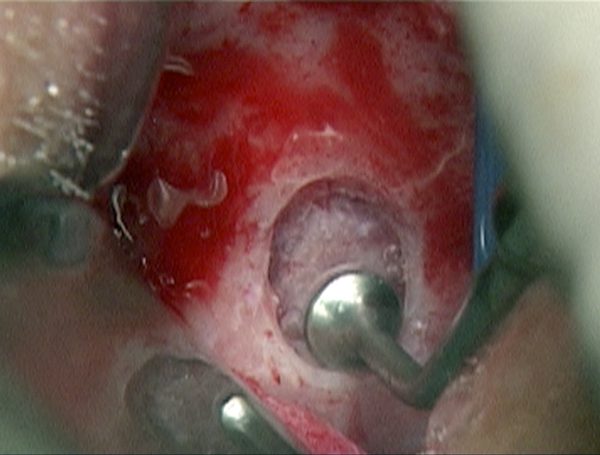

Immagine 5 Fenestrazione per rialzo sinusale con chirurgia piezoelettrica (Piezosurgery®)